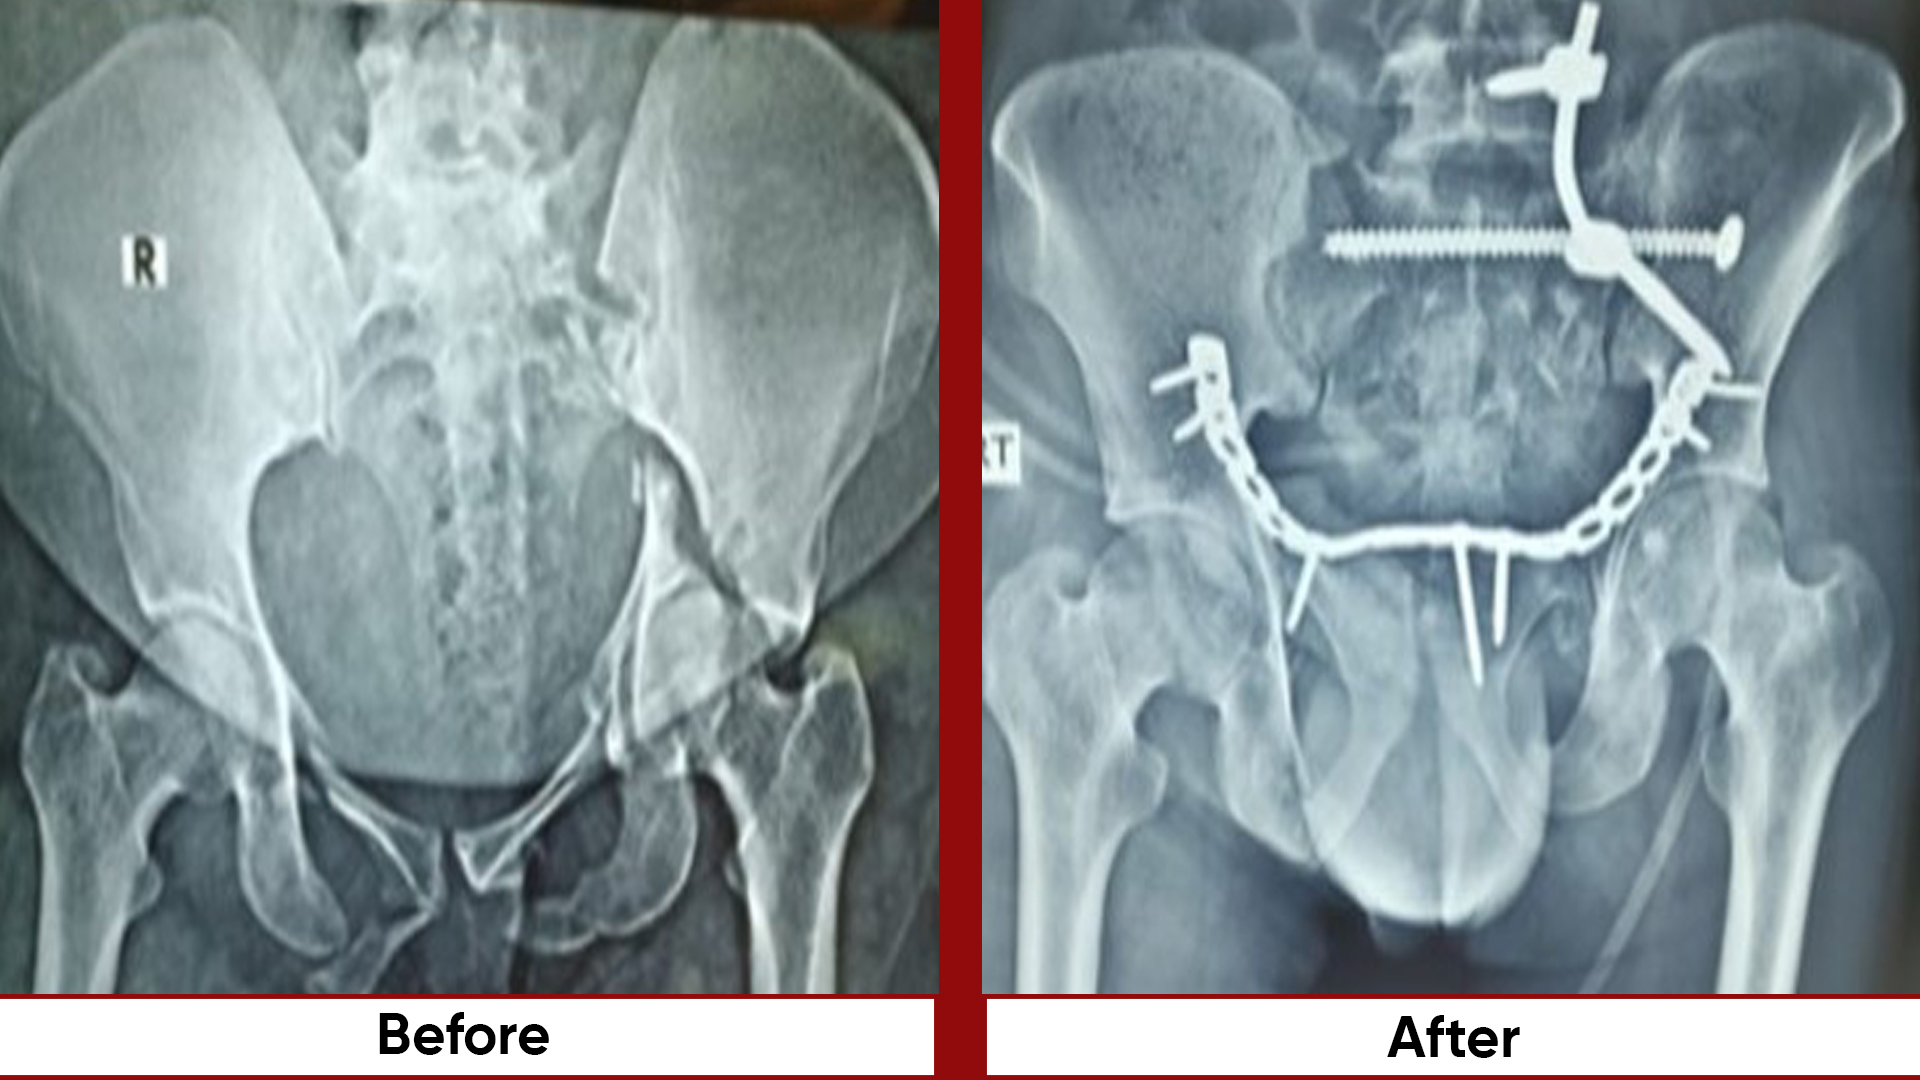

• Pelvic & Acetabular Fracture Fixation